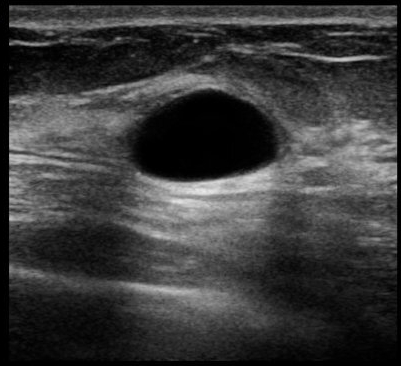

Не совсем типичный рак на УЗИ молочной железы

Всем привет, давно ничего не писал - было крайне лень. Этот пост будет интересен прежде всего врачам УЗД, конечно, ну и еще может врачам-онкологам и маммологам. На днях как обычно работал, и у одной пациентки обнаружилась интересная картина, достаточно нетипичная, если оценивать её с точки зрения УЗИ-признаков рака молочной железы. За несколько лет работы в онкологическом диспансере такое я вижу всего второй раз.

Итак, вот как оно выглядело:

Казалось бы, неровные, нечеткие, лучистые контуры, что необычного? Да просто оно по эхогенности ближе к окружающей ее фиброзной ткани, то есть, белое, яркое, если говорить простым человеческим языком. И его достаточно легко пропустить на УЗИ. Я его увидел только благодаря сердцевинке, которая была более темной, хотя на данном снимке это не особо заметно.